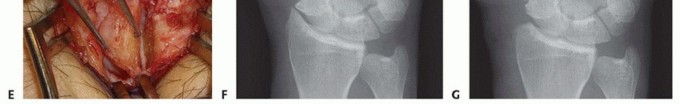

While radial styloidectomy is primarily an excisional procedure, "fixation" in this context refers to the meticulous repair of the capsular structures and, when performed adjunctively, the stabilization of concurrent reconstructive work. The dorsal radiocarpal capsule is carefully reapproximated using interrupted 3-0 or 4-0 absorbable sutures. A robust capsular closure is vital to prevent postoperative synovial fistulas and to restore a degree of secondary dorsal stability. The extensor retinaculum is then repaired, taking care not to overly constrict the first dorsal compartment, which could precipitate de Quervain's tenosynovitis. The skin is closed with a running subcuticular suture, and a bulky, well-padded short-arm volar splint is applied.

Complications, Incidence Rates, and Salvage Management

Despite its conceptual simplicity, radial styloidectomy carries a distinct profile of potential complications that can profoundly impact patient outcomes. The most frequent and arguably most distressing complication is injury to the Radial Sensory Nerve (RSN). The incidence of RSN neuropraxia or neuroma formation ranges from 5% to 15% in the literature, largely dependent on the care taken during the superficial dissection. A symptomatic neuroma can be utterly debilitating, causing intractable neuropathic pain that eclipses the original arthritic symptoms. Management of an established neuroma is notoriously difficult, often requiring surgical exploration, neuroma excision, and nerve end burying into the brachioradialis muscle belly or adjacent bone.

Image

The most catastrophic biomechanical complication is iatrogenic ulnar translation of the carpus. This occurs when the surgeon violates the 3-4mm safe zone, inadvertently detaching the origin of the Radioscaphocapitate (RSC) and Long Radiolunate (LRL) ligaments. Once these critical restraints are lost, the carpus invariably slides ulnarly down the slope of the radial articular surface. This leads to rapid, global radiocarpal and midcarpal arthrosis. Salvage for this disastrous complication is highly complex and typically necessitates a total wrist arthrodesis or a radiolunate arthrodesis to halt the ulnar slide and stabilize the carpus.